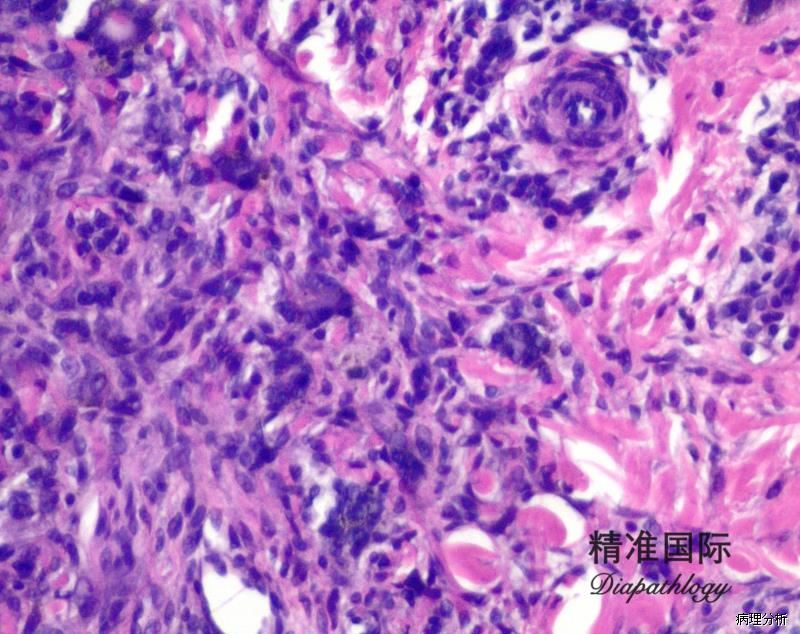

肿瘤由形态一致的梭形肌纤维母细胞和纤维母细胞所组成,瘤细胞长轴与表皮平行

细胞无明显异型性,无或很少核分裂像;

可有散在的淋巴、浆细胞,无泡沫样组织细胞或巨细胞。